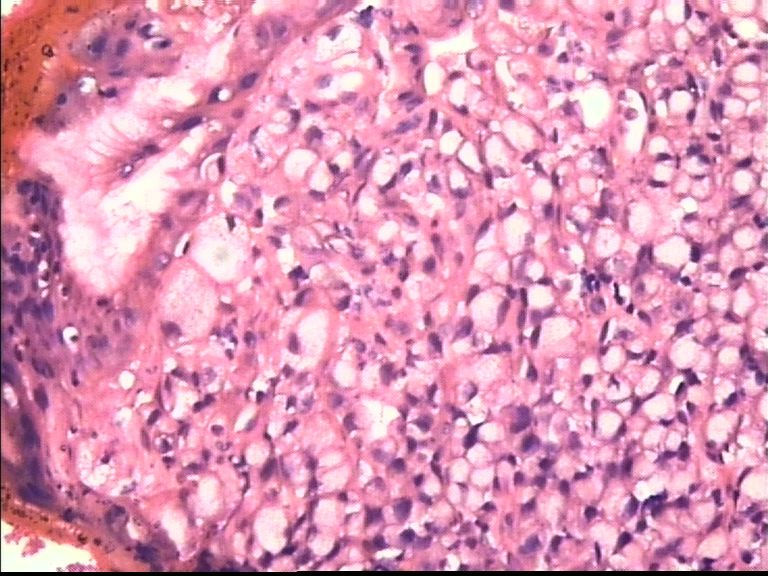

胃部溃疡3cm 53岁 男

• 胃部溃疡3cm 53岁 男图2

图2

仅此局部形态,应该是印戒细胞癌,最好有更多的背景资料

印戒细胞癌

倾向印戒细胞癌

诊断印戒细胞癌

印戒细胞癌高度可疑,建议做:CK、CD68、PAS帮助诊断。